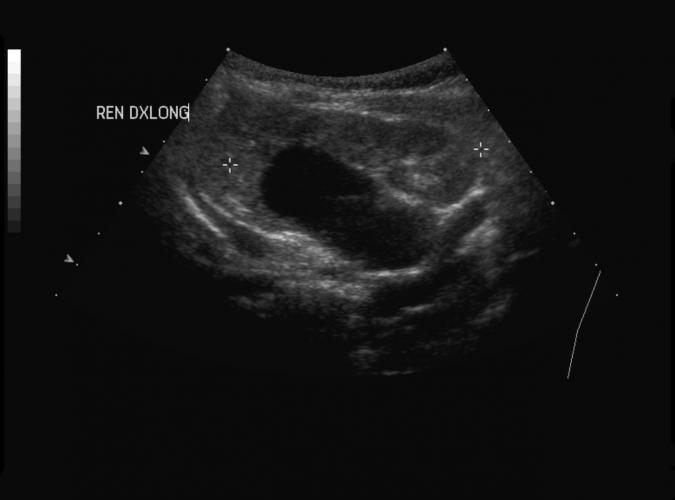

Patologi.

Samma patient som i 9e. Höger njure med en högfrekvent transducer visar små cystor,som är typisk för polycystiska

njurar.